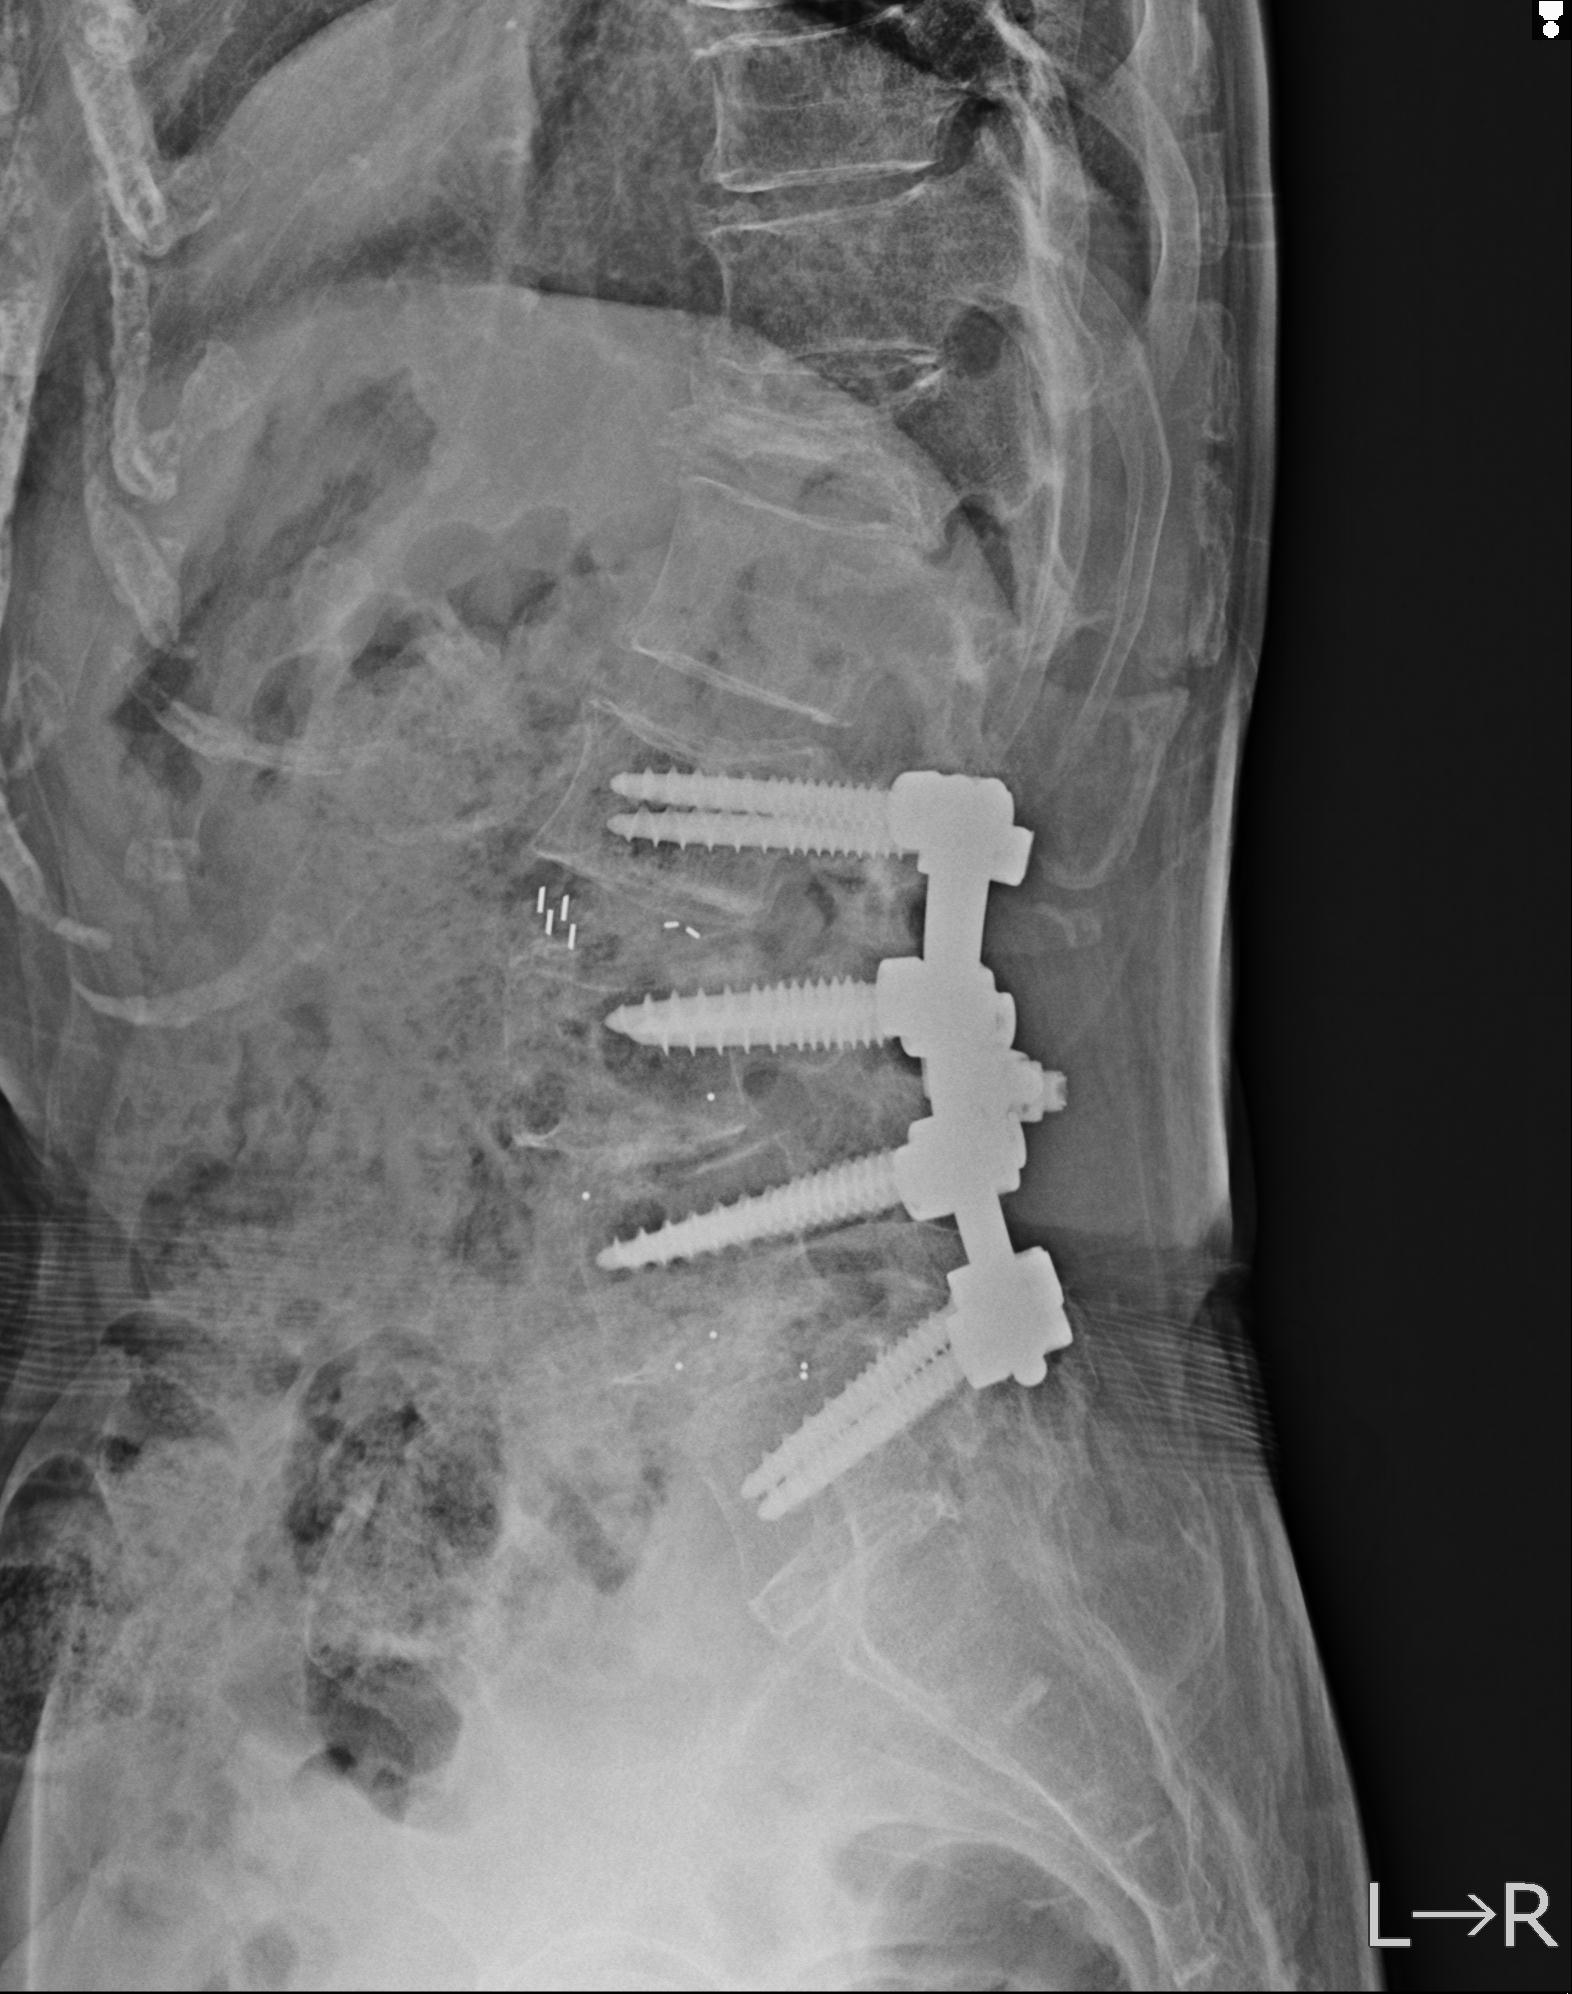

93804 2/9 腰椎 2R 後方固定 67歳女性